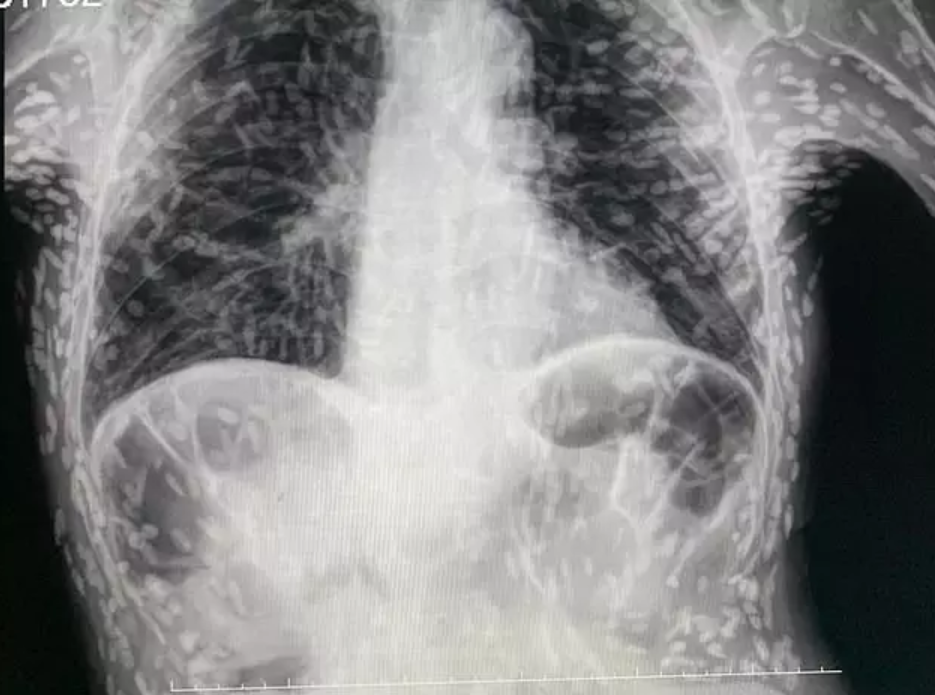

Jedan je čovjek došao u bolnicu s nečim što je mislio da bi mogao biti kroničan kašalj, ali zapravo se pokazalo da u njemu rastu na deseci trakavica. Užasavajuću rendgensku snimku otkrića podijelio je na Twitteru dr. Vitor Borin P. de Souza, djelatnik bolnici das Clínicas Botucatu u São Paulu, u Brazilu. Pacijent koji ništa nije sumnjao bolovao je od cisticerkoze, također poznate kao taeniasis.

Ali mogu izaći iz crijeva i otputovati drugamo, poput očiju, pluća, mozga i leđne moždine, a ciste koje ostanu mogu uzrokovati probleme ako se tamo razviju. Ciste poput kvržica stvaraju se oko ličinki kako bi im pomogle da prežive u tijelu, a one se mogu napipati kroz kožu. Svaka od bijelih točkica na užasavajućoj rendgenskoj snimci predstavlja cistu i kalcificirane ostatke parazita. Ciste mogu potrajati mjesecima ili čak godinama da se razviju nakon gutanja jajašca trakavice, ali se mogu lako ukloniti operacijom ili lijekovima.